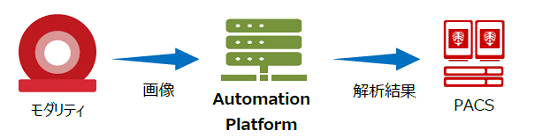

(1)自動化されたオープンなプラットフォーム 「Abierto Automation Platform」

Abierto Automation Platformは、CTなどの医用画像診断装置で撮影された画像データを受信し、自動でアプリケーションを起動する。そのアプリケーションの処理結果として病態に係わる情報、評価または診断を行うための情報を提供。オープンなプラットフォーム上には、自社のみならずパートナー会社のアプリケーションの搭載も可能である。